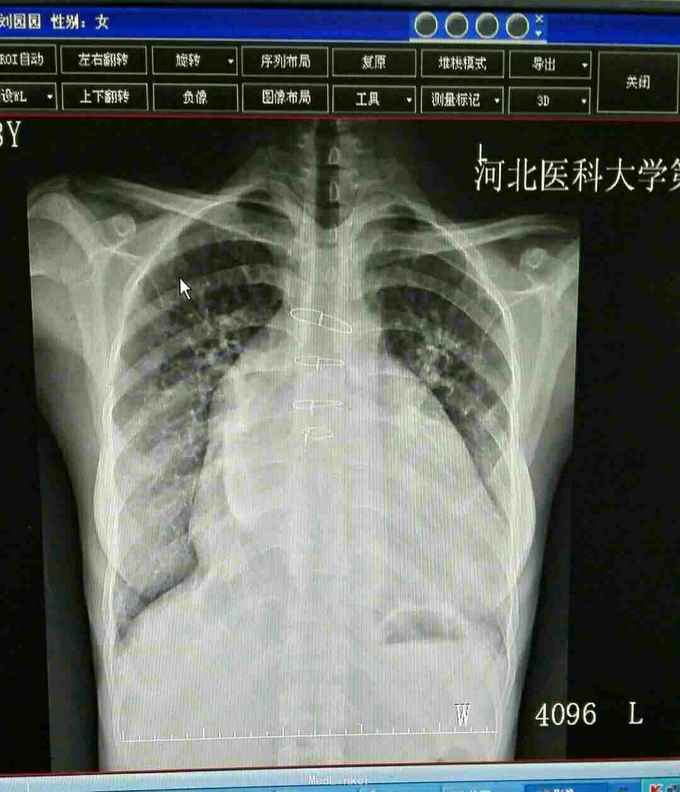

查体 生命体征平稳,口唇无发绀,双肺呼吸音清,未闻及干湿性罗音,心律不齐,于心尖处可闻及3/6级收缩期杂音,肺动脉瓣第二心音亢进,腹部平软无压痛反跳痛,肝脾肋下未闻及肿大。 辅助检查 心脏彩超 先天性心脏病 室间隔缺损修补术后 三尖瓣赘生物形成,三尖瓣反流 二尖瓣反流。 胸片示 全心增大 肺部瘀血。

诊断先天性心脏病 室间隔缺损修补术后 三尖瓣赘生物形成 三尖瓣反流 二尖瓣反流 治疗 患者入院后完善各项术前检查及准备在全麻体外循环下行二尖瓣置换术 三尖瓣置换术 手术过程 患者取平卧位于手术台,常规消毒铺单,摇摆钜开胸骨进胸,小心分离胸骨下粘连组织,心外探查 全心增大,右心房及左心房重度增大,常规建立体外循环,阻断升主动脉冷灌心脏停跳,切开右心房放置左心引流,切除病变的二尖瓣及三尖瓣以机械瓣膜置换之,开放升主动脉,除颤心脏复跳,辅助循环,生命体征稳定后,减量停机,撤除体外循环管道,彻底止血关胸,患者安反监护室。